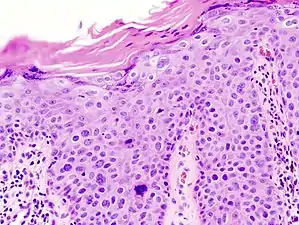

Histopathologically, the epidermis in cSCC in situ (Bowen's disease) will show hyperkeratosis and parakeratosis. There will also be marked acanthosis with elongation and thickening of the rete ridges. These changes will overly keratinocytic cells which are often highly atypical and may in fact have a more unusual appearance than invasive cSCC. The atypia spans the full thickness of the epidermis, with the keratinocytes demonstrating intense mitotic activity, pleomorphism, and greatly enlarged nuclei. They will also show a loss of maturity and polarity, giving the epidermis a disordered or "windblown" appearance.

Two types of multinucleated cells may be seen: the first will present as a multinucleated giant cell, and the second will appear as a dyskeratotic cell engulfed in the cytoplasm of a keratinocyte. Occasionally, cells of the upper epidermis will undergo vacuolization, demonstrating an abundant and strongly eosinophilic cytoplasm. There may be a mild to moderate lymphohistiocytic infiltrate detected in the upper dermis.[12]

Bowen's disease is essentially equivalent to and used interchangeably with cSCC in situ, when not having invaded through the basement membrane.[12] Depending on source, it is classified as precancerous[13] or cSCC in situ (technically cancerous but non-invasive).[47][48] In cSCC in situ (Bowen's disease), atypical squamous cells proliferate through the whole thickness of the epidermis.[12] The entire tumor is confined to the epidermis and does not invade into the dermis.[12] The cells are often highly atypical under the microscope, and may in fact look more unusual than the cells of some invasive squamous-cell carcinomas.[12]

In invasive cSCC, tumor cells infiltrate through the basement membrane. The infiltrate can be somewhat difficult to detect in the early stages of invasion: however, additional indicators such as full thickness epidermal atypia and the involvement of hair follicles can be used to facilitate the diagnosis. Later stages of invasion are characterized by the formation of nests of atypical tumor cells in the dermis, often with a corresponding inflammatory infiltrate.[12]